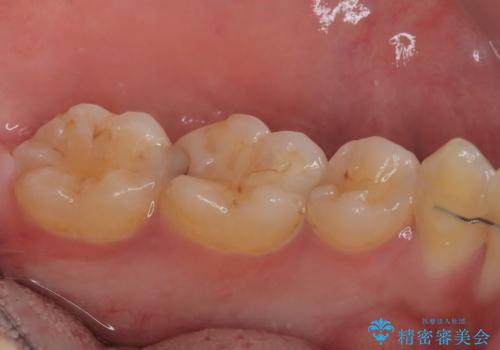

- 当院で矯正治療を終えて、左下が虫歯になっている気がするとのことで来院された患者様です。レントゲン検査の結果、コンポジットレジンによる修復箇所が複数行われており、詰め物の下に虫歯を認めました。

拡大鏡視野下でコンポジットレジン、虫歯の除去を行い、オールセラミッククラウンに適した形に整えました。

歯と歯茎の間に圧排糸と言われる糸を入れてシリコーン印象材にて精密な型どりをしました。